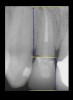

Figure 4  CLINICAL GUIDELINES  The minimum distance needed is 2.5 mm from the osseous crest to the final margin placement to avoid biologic-width impingement. This measurement is meant as a guideline and not an absolute number, as it has been shown to have individual variability. This gives a clinical guideline of 4 mm consisting of 1.5 mm of tooth structure and 2.5 mm biologic width.

Figure 4

Figure 5  CLINICAL GUIDELINES  The minimum distance needed is 2.5 mm from the osseous crest to the final margin placement to avoid biologic-width impingement. This measurement is meant as a guideline and not an absolute number, as it has been shown to have individual variability. This gives a clinical guideline of 4 mm consisting of 1.5 mm of tooth structure and 2.5 mm biologic width.

Figure 5

If the tooth has been endodontically treated, the remaining tooth structure relative to the post space needs to be evaluated. The Rule of Thirds is used in this situation. It states that the canal or canal space preparation should not be any wider than one third the mesiodistal root diameter after the endodontic access (Figure 3).3 Once the clinician determines whether adequate tooth structure is present, the second area to evaluate is the distance of the fracture/caries from the crest of bone. To avoid biological width impingement, the minimum distance needed from the osseous crest to the final margin placement is 2.5 mm (Figure 4). As determined in cadaver studies, this consists of approximately 1 mm of connective tissue attachment, 1 mm of junctional epithelium, and 0.5 mm of gingival sulcus.4 This measurement is meant as a guideline and not an absolute number, as it has been shown to have individual variability.5 This actual dimension for the individual patient can be predictably determined by sounding to bone on the adjacent teeth to more closely determine the individual’s biologic width.6

The clinical guideline of 4 mm—consisting of 1.5 mm of tooth structure and 2.5 mm biologic width1,3—is, therefore, the minimum limit for tooth structure above the alveolar bone (Figure 5). If this parameter cannot be met, there are two options for obtaining this threshold. One option is surgical crown lengthening,7,8 and the other is forced orthodontic eruption.9 The choice between each option should be made based on the effect each procedure will have on the esthetics of the case, the crown-to-root ratio, and whether osseous surgery will create a furcation involvement on the adjacent teeth (Figure 6). Esthetic considerations will be addressed later. In terms of crown-to-root ratio, there are two guidelines that exist for determining the minimum ratio (Figure 7). One is the classical 1:1 presented by Penny.10 The second, for maxillary anterior teeth, is 12 mm to 13 mm of tooth with 8 mm to 9 mm of root in bone and 4 mm coronal to the bone, as presented by Spear.1 If all of these criteria for tooth structure are met, then the tooth should be considered an acceptable candidate for retention and restoration. Also, if insufficient tooth structure exists, the required tooth structure can be obtained via forced orthodontic eruption or periodontal surgery provided that the esthetics and periodontal function of the tooth in question and the adjacent dentition are not compromised.